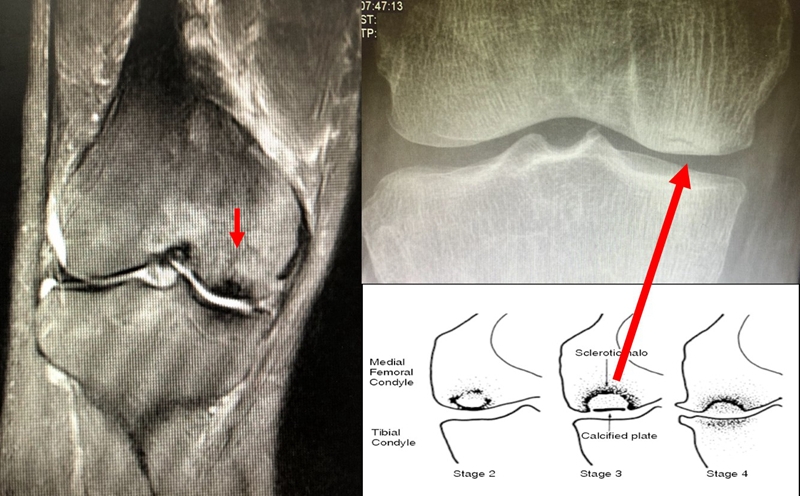

病例:女,65岁,主诉左膝关节内侧疼痛2月余。2017年11月X光未见左膝骨质异常。MR见股骨内侧髁骨坏死,半月板相对突出百分比(RPE)28.3%,合并内侧半月板后根部撕裂,矢状位病变区域前后径为11.67mm,关节线会聚角2.68°

予消炎止痛药物口服、静滴唑来膦酸钠注射液,避免负重6周,后改部分负重,12周后全负重。

2018年2月复查MR见骨髓水肿明显吸收,坏死灶边界清晰,半月板相对突出百分比(RPE)28.92%

2018年6月复查MR见骨髓水肿基本完全吸收,坏死区修复良好,半月板相对突出百分比(RPE)38.54%,患者临床症状消失。

提示坏死好转了,但半月板突出进展了,膝关节的退变加重了。